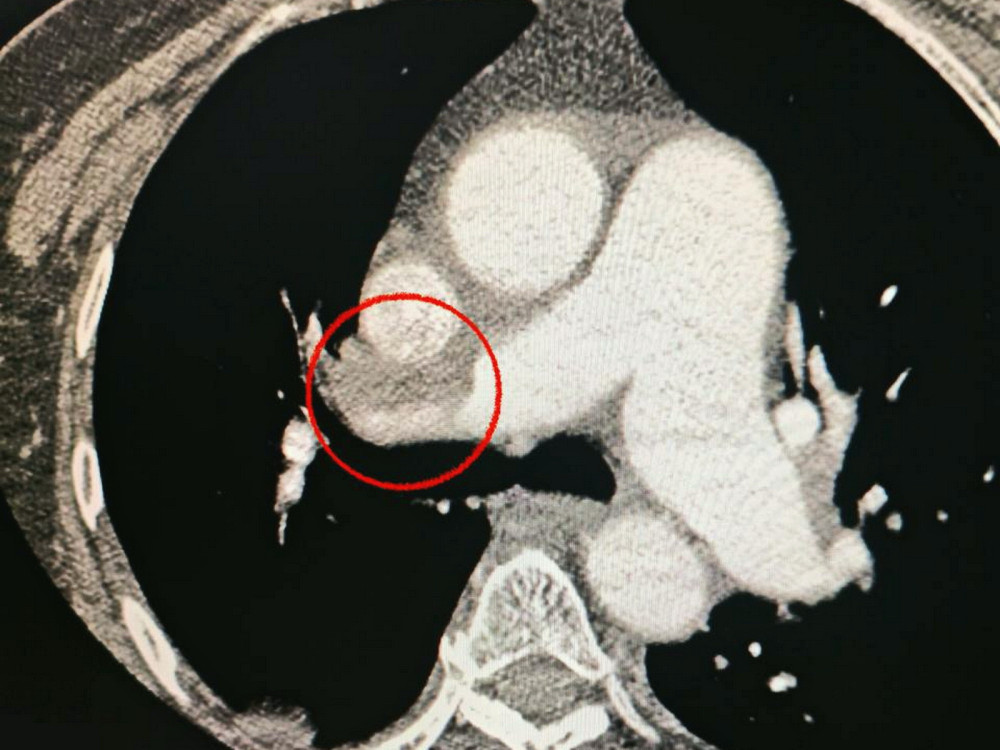

Крім того, лікарі зауважили, що у пацієнтки виникли проблеми з диханням, тому додатково провели обстеження легень. Виявилося, що у неї була тромбоемболія легеневої артерії.

Команда лікарів вирішила провести одночасну тромбектомію на обох артеріях, що було вкрай необхідно для порятунку життя.